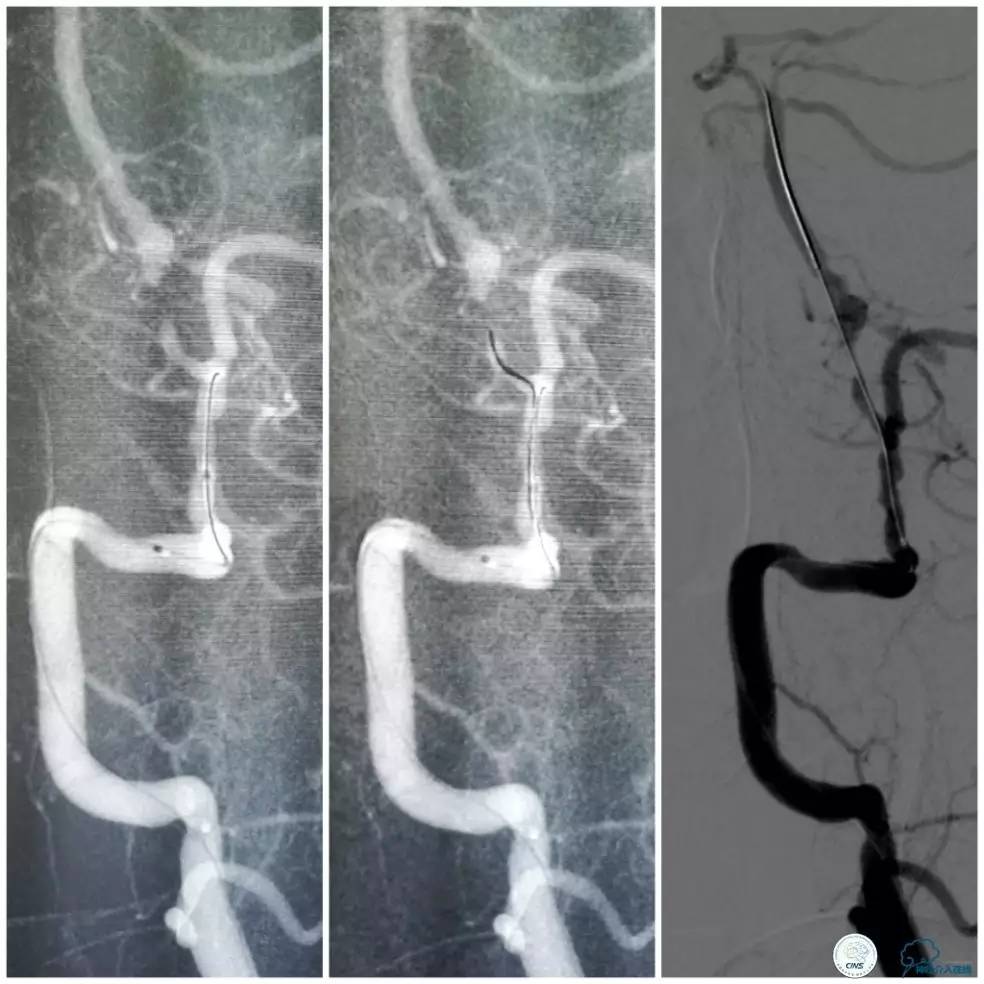

遂再次将Transend微导丝送至右大脑后动脉P1段,使用Gateway球囊(2.0mm×15mm)于支架最狭窄处后扩张(图15)。

图15

其后造影显示支架贴壁良好,远端血管显影好,前向血流TICI3级(图16)。

图16

缓慢回撤6F导引导管至锁骨下动脉,造影显示右椎V1段支架无移位,前向血流正常(图17)。

图17